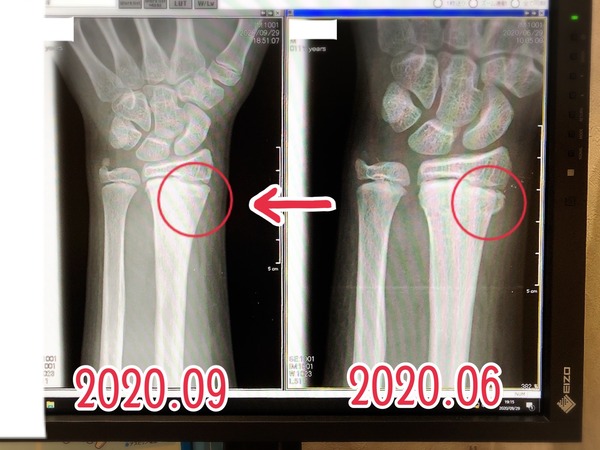

今年の6月後半に、

息子が左の前腕、

手首に近いあたりを若木骨折しました。

1年前の6月後半に

左の前腕を若木骨折したのに⁉︎また⁉︎

そして、先週の診察で、

折れた部分も順調に回復してるし、

成長にも影響はなさそうなので、

今回で診察は終了です。